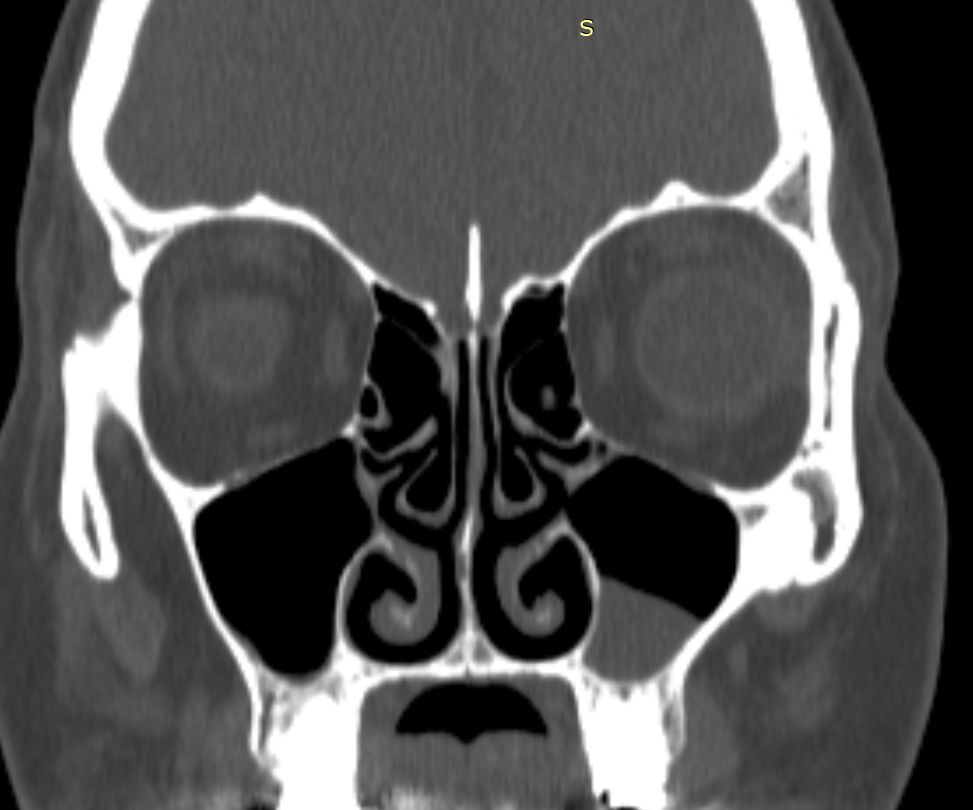

КТ-снимки хронического этмоидита: подробная визуализация